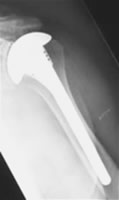

Im Spätstadium der Arthrose mit Aufbrauch des Gelenkknorpels und „Knarren“ sowie Bewegungseinschränkung ist auch hier der Gelenkersatz, d.h. der Einbau eines künstlichen Gelenkes, ähnlich wie an Knie und Hüfte, möglich.